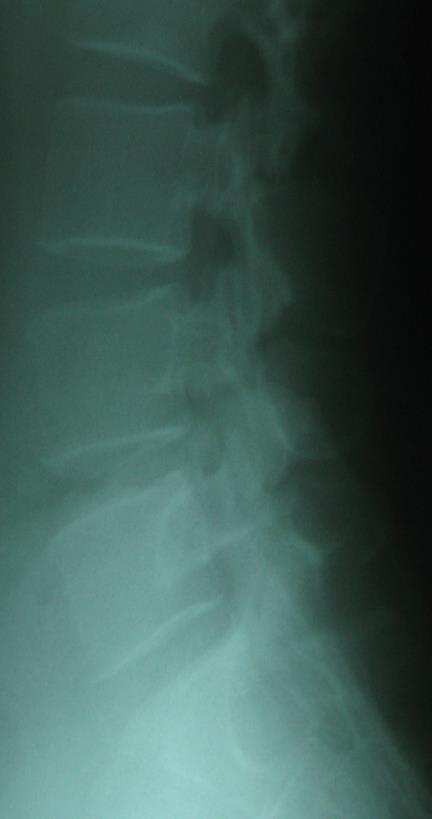

30대 초반 여성으로 몸무게가 거의 100Kg에 육박하는 환자입니다. 타한의원에서 골반이상으로 인한 슬통이라고 진단받고 20여 회 추나 치료 후 호전 없어 내원했다 합니다. 약간의 무릎부종이 있었고 연골도 많이 약화된 상태였습니다. 체중 검사시 반대측으로 몸무게가 (15Kg이상) 차이가 났으며 이런 경우는 슬관절 자체의 문제로 인한 통증일 가능성이 높습니다.

슬관절 문제시 고관절 문제를 확인해 봐야 하는데 좌측 고관절 외회전시 별무이상이나 내회전시 통증을 유발하였다. 고관절 주변 근육부터 먼저 침치료 해 보니 무릎을 굽힐 때의 통증이 많이 감소되었다. 골반교정을 위해 본원에 내원하셨지만 이 분은 무릎통증이 골반교정과는 무관한 경우였습니다. 이후 한달 정도의 치료 후 제 증상은 호전되었고 지금은 체중감량을 위해 비만치료를 하고 계십니다.